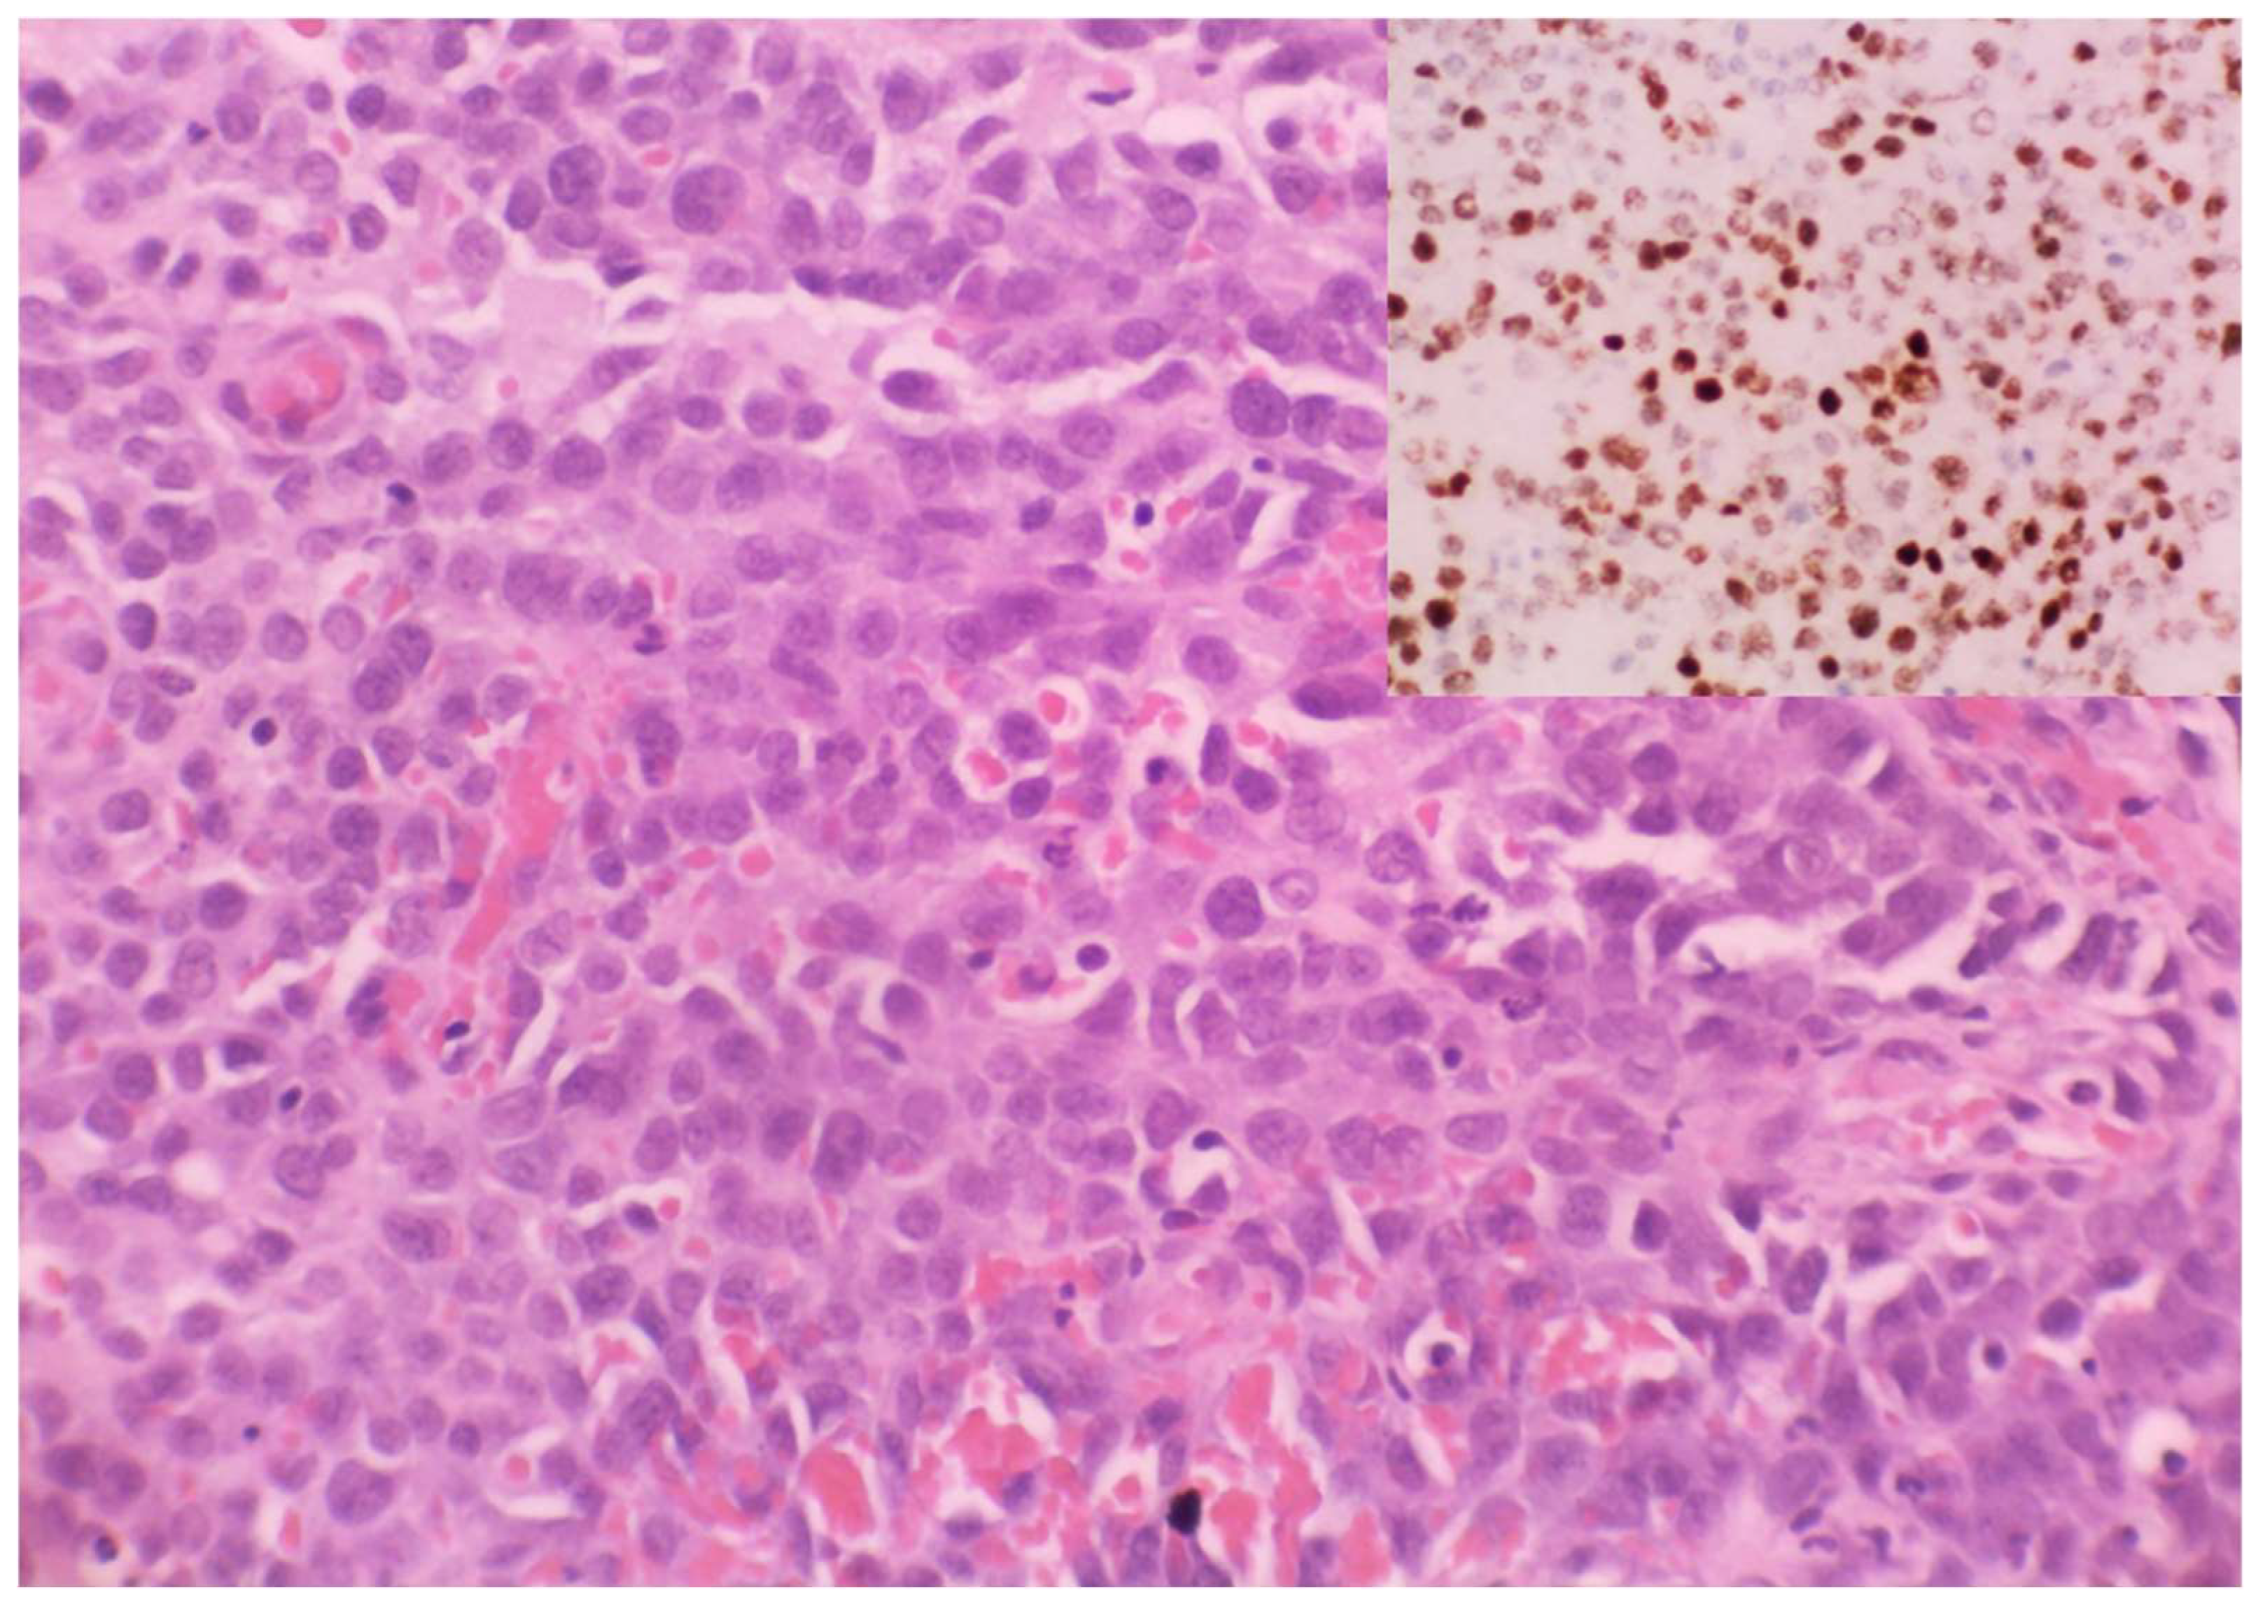

Figure 3.

Anaplastic KS: Plump undifferentiated epithelioid cell morphology (haematoxylin and eosin). HHV8 positivity confirming KS (Inset, HHV8).